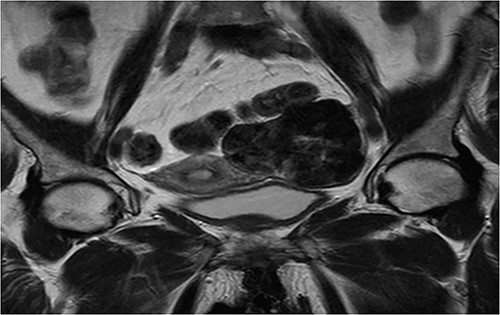

An abdomino-pelvic ultrasound was performed showing a pelvic lesional process with a left-lateralized supra uterin location, with a mixed echo-structure, mainly of tissue, classified O-RADS 5 (Figs 1 and 2).

Coronal T2 sequence: left uterine mass, heterogeneous, in T2 hyposignal containing areas in hypersignal.